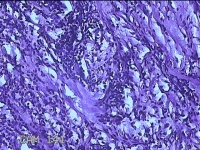

右侧手掌肉芽组织

性别

女

年龄

48岁

临床诊断

手掌开放性损伤

一般病史

右侧手掌肉芽组织增生

标本名称

大体所见

灰白暗红色带皮肤样组织1.3x0.8x0.3cm一块,切面灰白粉红色,质软。

图2